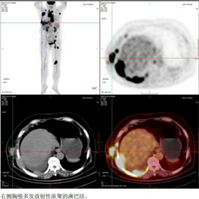

65岁女性患者,2024年8月出现下腹部不适,后出现右上腹痛并加重,近1月体重下降8斤。2024年12月就诊完善检查:乙型肝炎病毒表面抗原阳性(乙肝病毒DNA <500 IU/ml),β2-微球蛋白4.27 mg/L↑,乳酸脱氢酶1011.90 U/L↑。超声提示双侧颈部、右腋下(最大5.7*4.8cm)、左腹股沟多发肿大淋巴结。右腋窝淋巴结穿刺病理诊断为弥漫性大B细胞淋巴瘤,免疫组化示:CD20(+)、CD10(-)、BCL6(+,约35%,热点区约60%)、MUM1(+)、BCL-2(+,约80%)、C-Myc(+,约40%)、P53(+,约10%)、Ki-67(+,约80%),符合non-GCB型(Hans分型)及双表达表型;EBER(-)。骨髓未见侵犯。PET-CT提示多发高代谢病灶,累及双锁骨上、纵隔、右腋窝、右胸壁、右眶内、右侧胸膜、心包、左腹股沟、左腘窝等多部位,伴心包及右侧胸腔积液;诊断为:非霍奇金淋巴瘤 弥漫性大B细胞淋巴瘤(non-GCB型,双表达,IV期A组,IPI评分4分高危),慢性HBV感染。

2024-12 PET-CT检查提示膈肌上下多发高代谢淋巴结